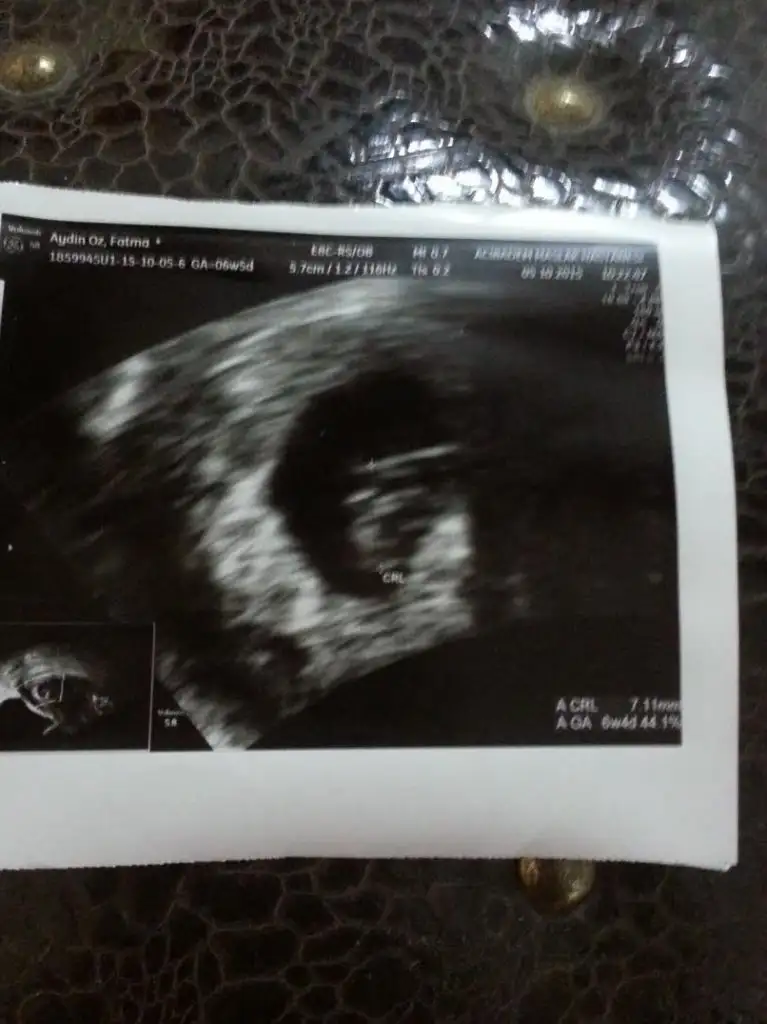

İlk görüntüler 6,5 haftalıkken, sonraki iki görüntü 8,5 haftalık olarak çekildi.

Tahmin yapabilir misiniz?